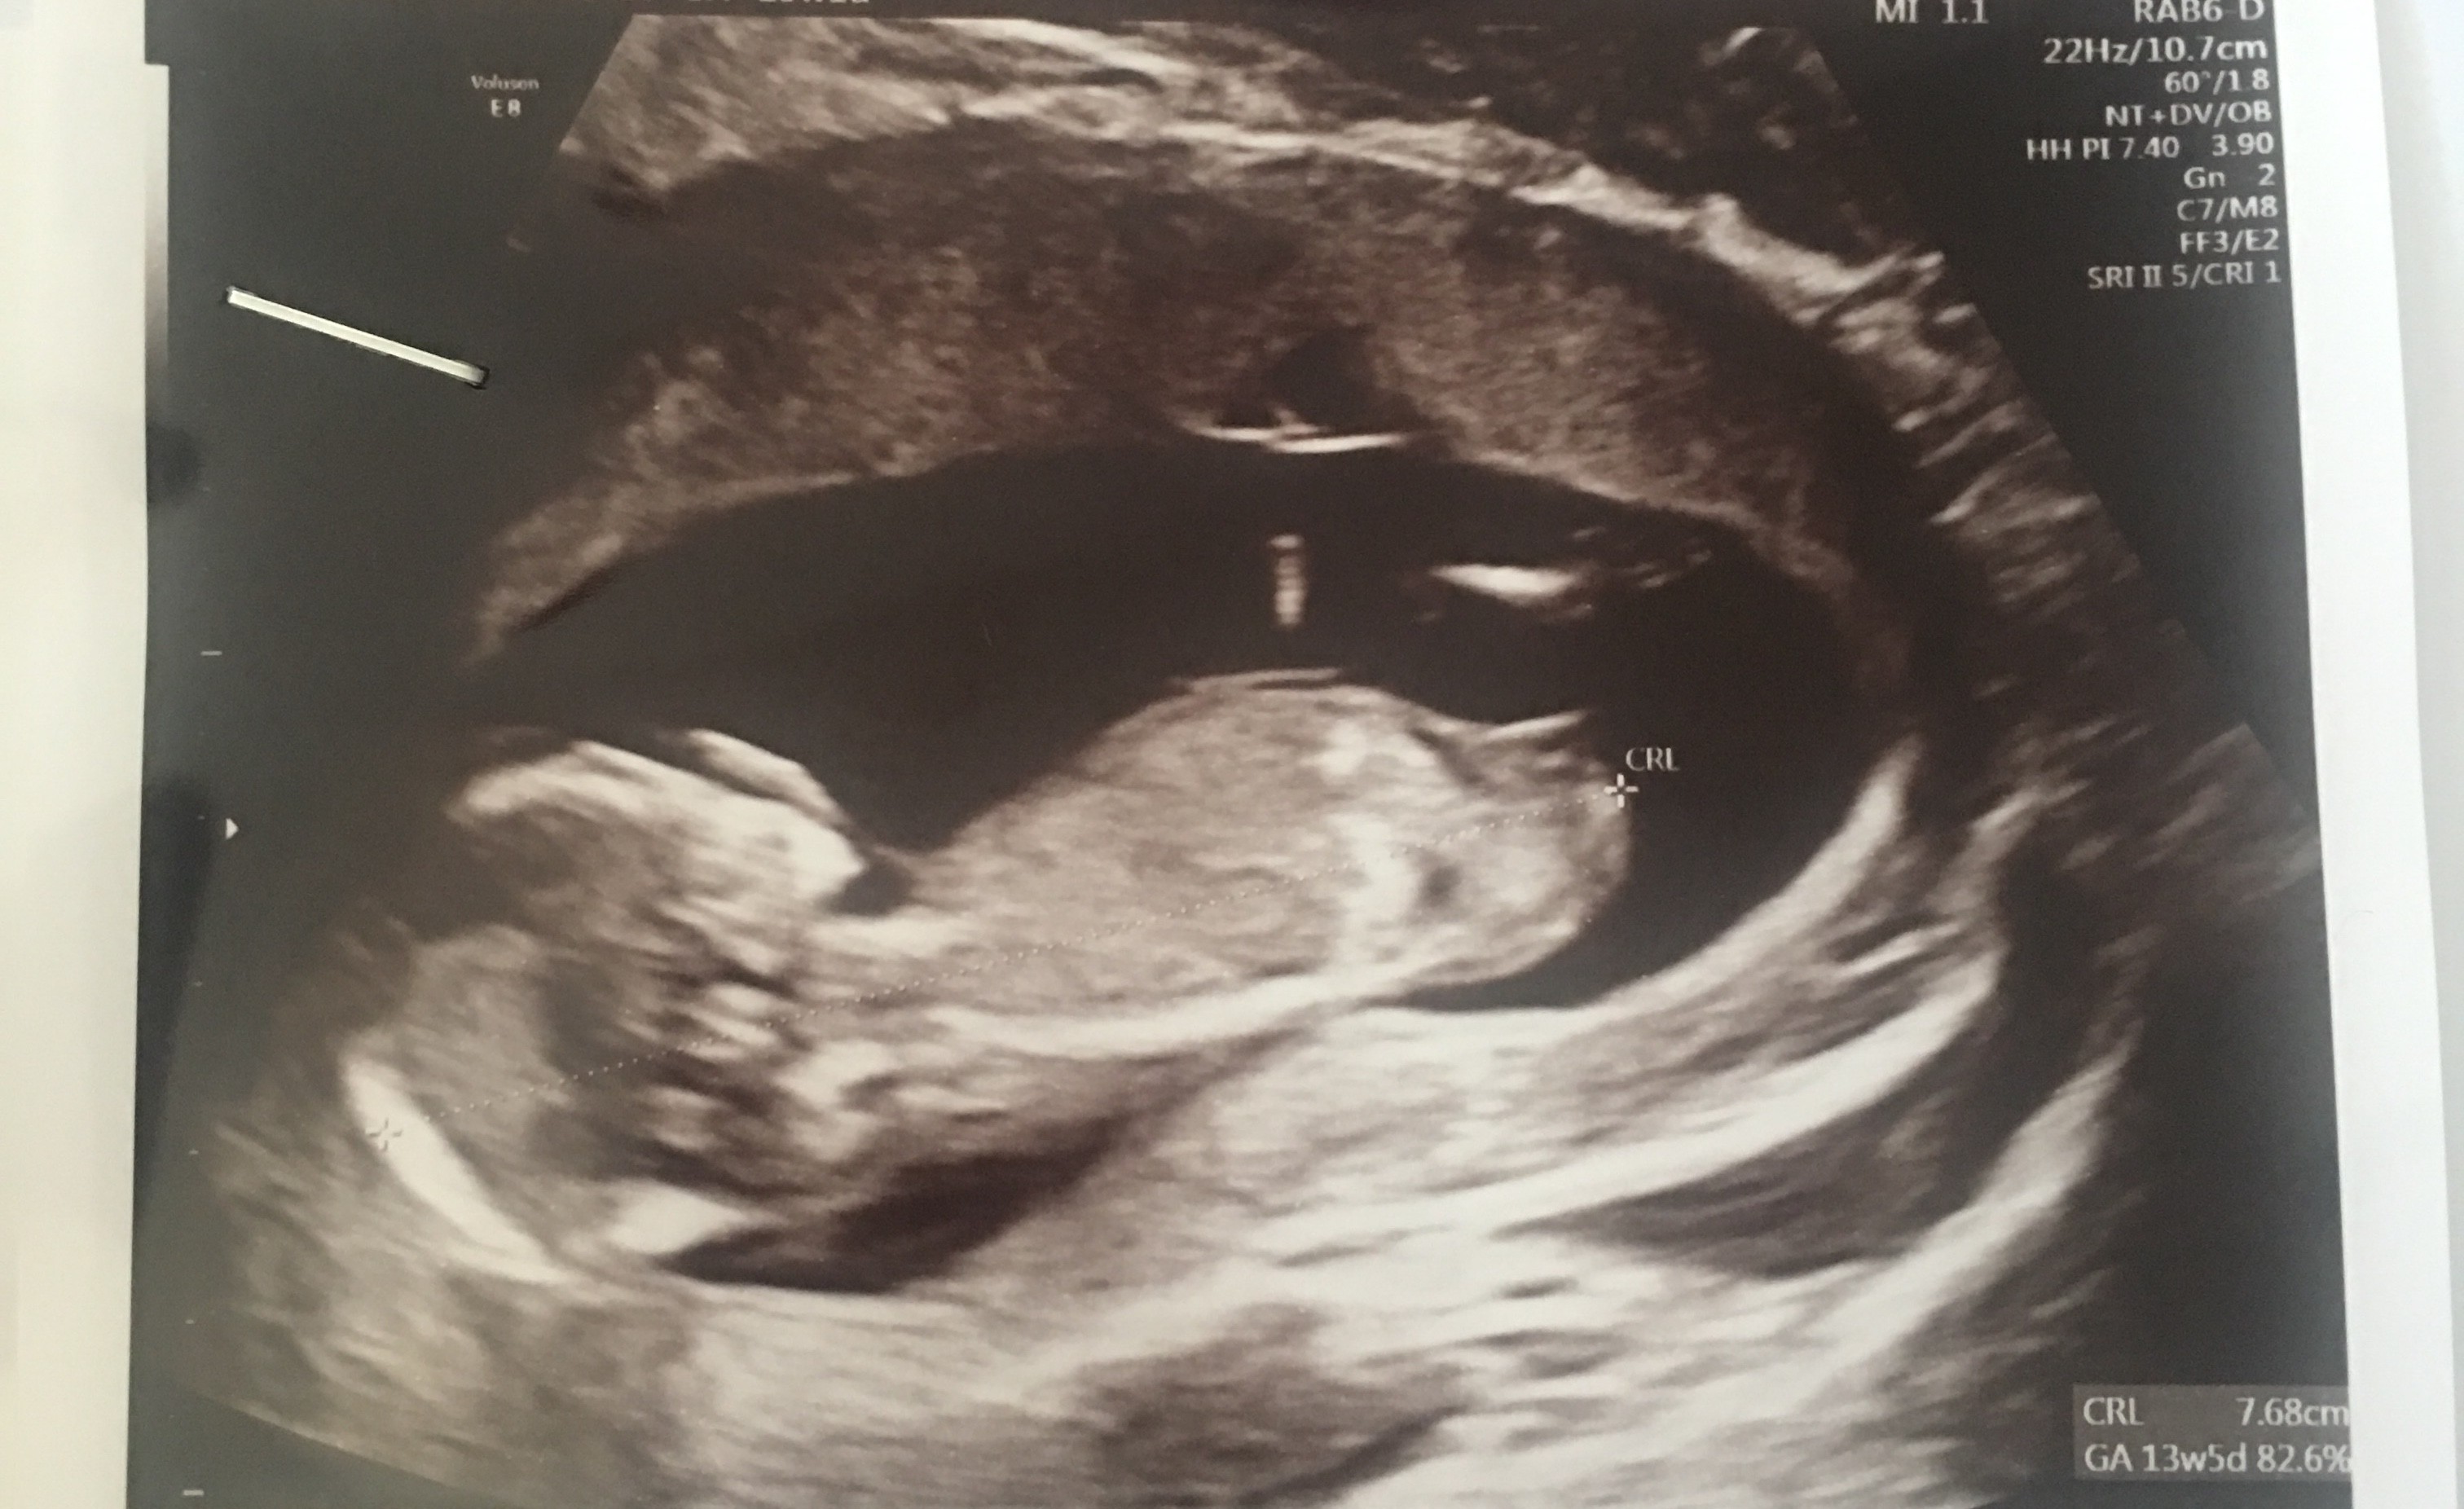

Witam w 19 tygodniu ciąży dowiedziałam się ze będę miała dziewczynkę w 20 tyg okazało się jednak , że to chłopak. Sama już nie wiem bo na jednym usg widać na pewno dziewuche a na drugim chłopca. Może to pempowina ?? Może ktoś mi pomoże rozwiązać ta zagadkę

Załączniki

• 4A8F5FF1-76CA-4DE0-AC12-5EDF08E820F2.jpg

4A8F5FF1-76CA-4DE0-AC12-5EDF08E820F2.jpg

596,4 KB · Wyświetleń: 44 144